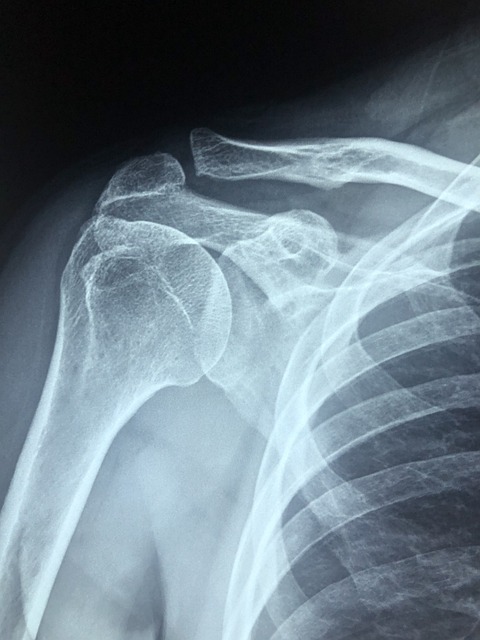

어깨는 생각보다 굉장히 복잡한 구조를 가지고 있어요.

팔을 자유롭게 움직이게 해주는 관절 중 하나인 ‘견관절’은 여러 개의 뼈, 근육, 인대, 힘줄이 정교하게 연결되어 있어요.

이중 한 군데만 문제가 생겨도 통증이 발생할 수 있기 때문에 원인을 파악하는 것이 중요합니다.

📌 회전근개 파열 (Rotator Cuff Tear)

- 어깨에 있는 4개의 근육(극상근, 극하근, 견갑하근, 소원근)을 회전근개라고 합니다.

- 반복적인 사용이나 갑작스러운 힘에 의해 찢어지거나 손상되면 통증이 발생합니다.

- 증상 : 팔을 들 때 통증이 심하고, 야간에 통증이 더 심해짐. 움직임이 제한됨.

📌 어깨 탈구

- 운동 중 사고나 넘어짐 등으로 어깨 관절이 빠지면서 생깁니다.

- 반복 탈구 가능성이 높고, 조직 약화로 이어질 수 있습니다.

- 증상 : 어깨가 빠진 듯한 느낌, 팔 움직임 제한, 극심한 통증.